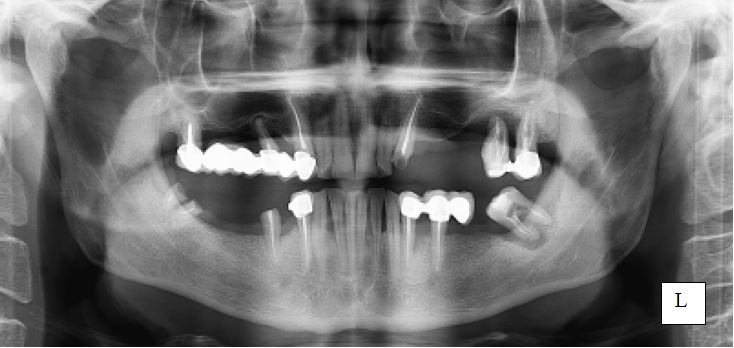

5. Назовите снимок, опишите 3.7 зуб

1. Панорамная томограмма ЗЧС

2. Антиретровирусная терапия. удаление зуба 3.7. Патогенетическая терапия кандидоза, противогрибковые средства.

5.Назовите снимок, опишите 3.6 зуб.

5. Внутриротовой дентальный снимок 3.6

6. Антиретровирусная терапия. удаление зуба 3.6. Патогенетическая терапия кандидоза, противогрибковые средства.

4.Назовите снимок, опишите 3.6 зуб.

4. Внутриротовая дентальная рентгенограмма зуба 3.6